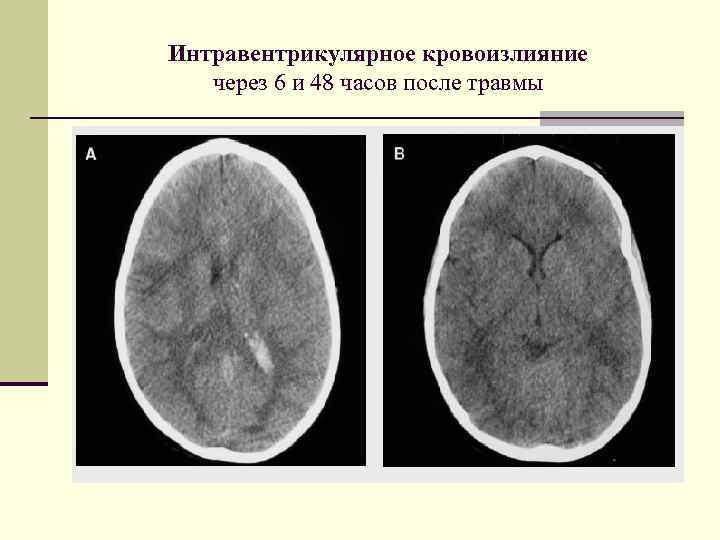

Интравентрикулярное кровоизлияние через 6 и 48 часов после травмы Интравентрикулярное кровоизлияние через 6 и 48 часов после травмы